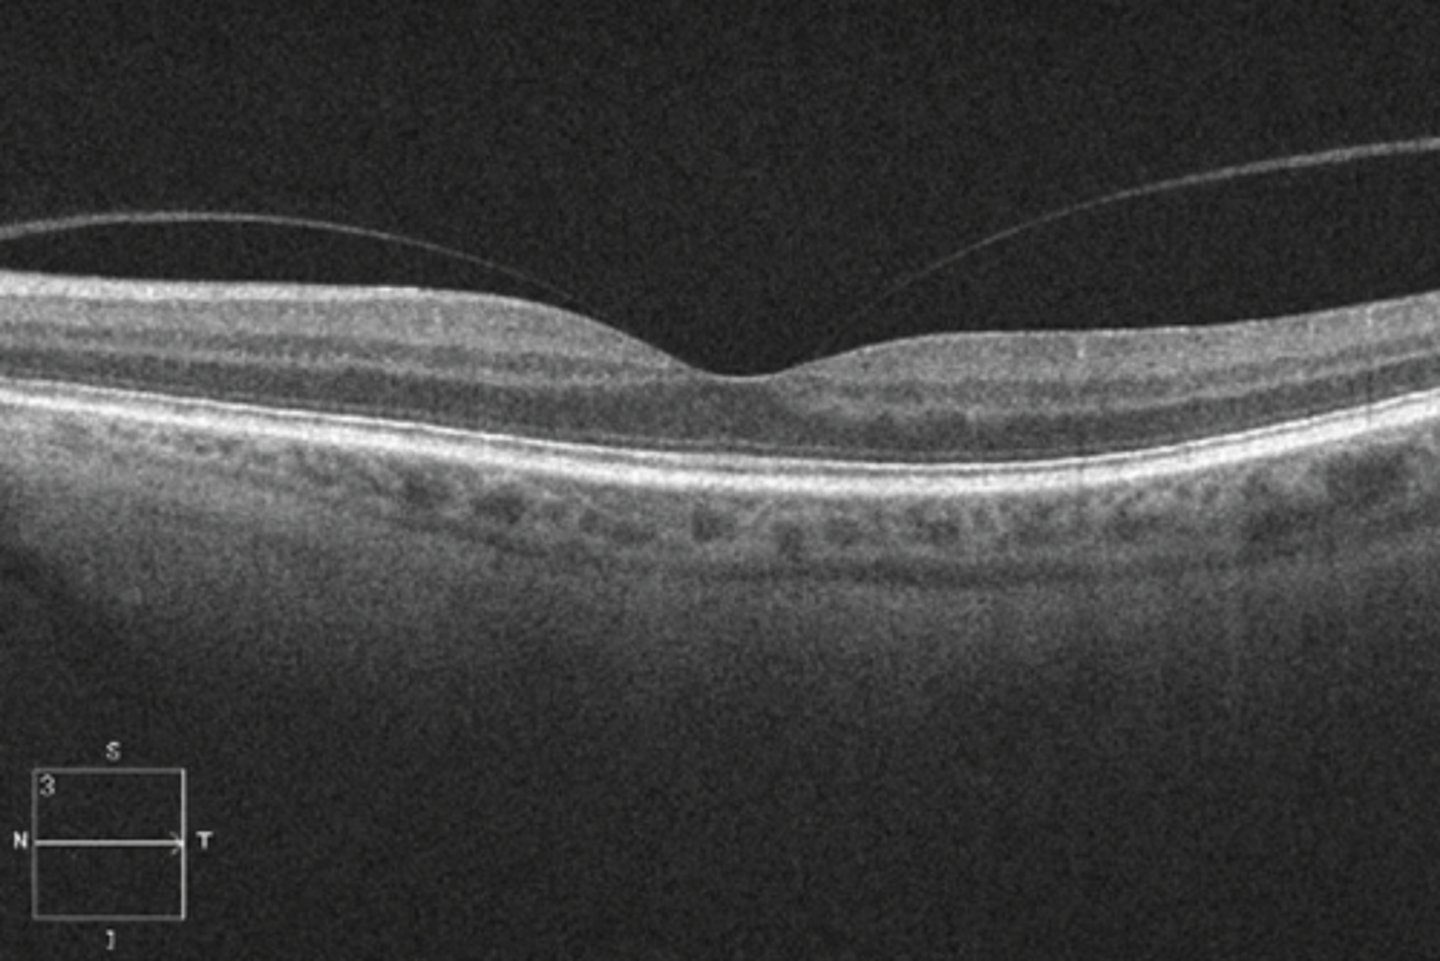

What does an epiretinal membrane (ERM) look like on OCT?

hyperreflective membrane within ILM (between RNFL and posterior hyaloid of vitreous) = more hyperR than vitreous face but same reflectivity as rNFL

What sign of epiretinal membrane (ERM) is shown here?

macular pucker = distorted retina = blur, distortion

macular pucker with retinal striae

macular pucker = pulling causes macular edema/cystic spaces